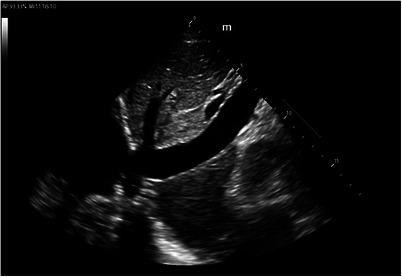

An unexpected etiology of generalized weakness.

J Am Coll Emerg Physicians Open. 2024 Jun 16;5(3):e13193. doi: 10.1002/emp2.13193. eCollection 2024 Jun.